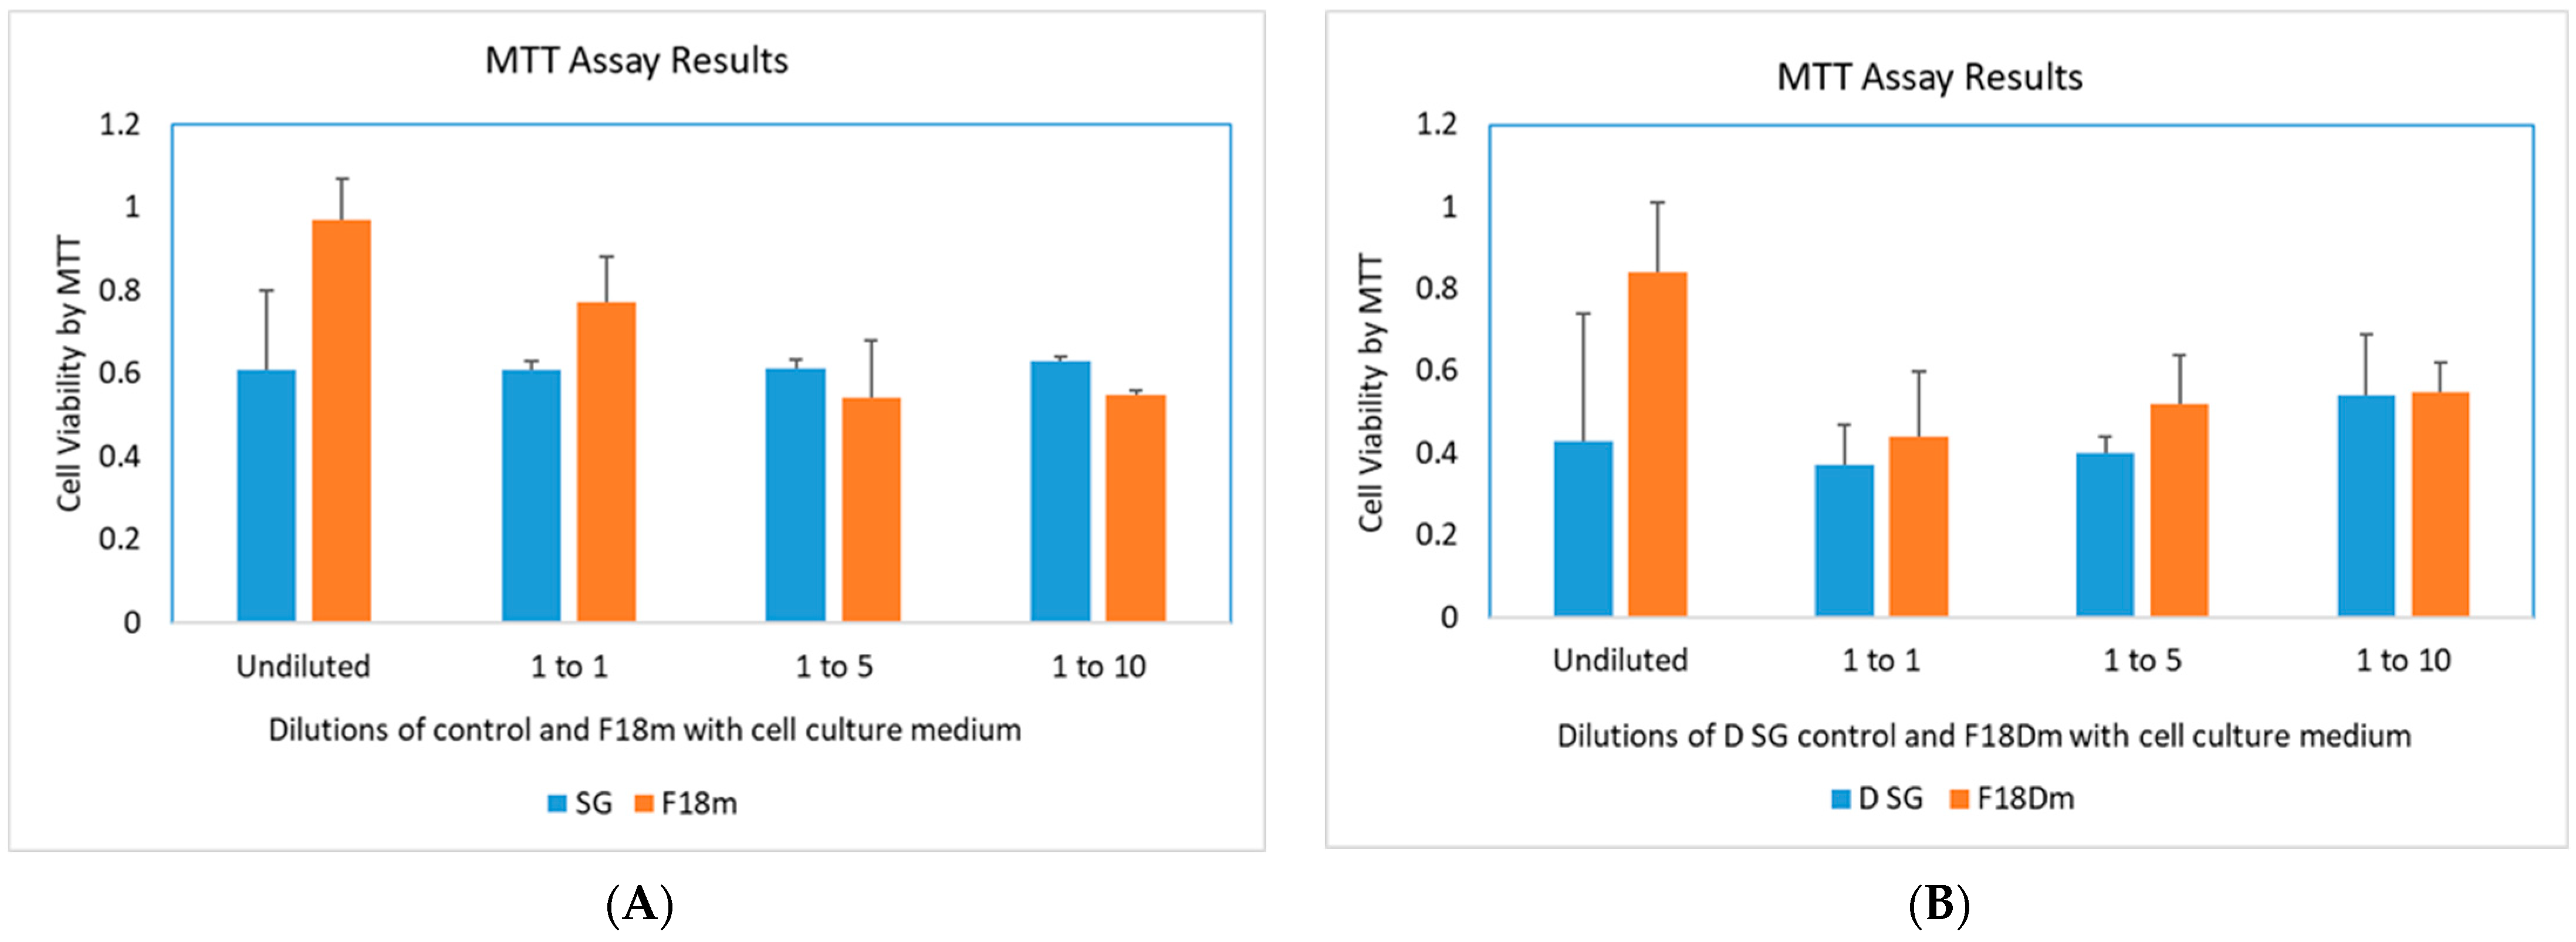

3.5. Post-Infection Antiviral Activity of F18m in Nasal Epithelial Primary Cells (HNpECs, PromoCell)

3.6. Cytotoxicity Study of F18m and F18Dm in Normal Saline